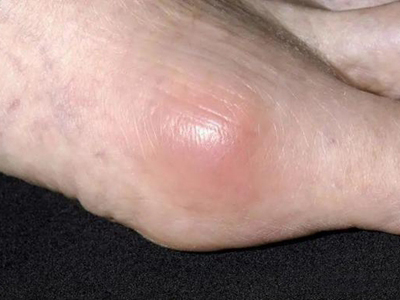

痛风病程较长,常反复发作而迁延不愈形成痛风石,是痛风的特征性临床表现,常见于指关节、第一跖趾关节、耳廓等处。外观为隆起、大小不一的不规则的黄白色赘生物,表面菲薄,破溃后排出白色粉状或糊状尿酸盐结晶物,经久不愈,但较少继发感染。部分患者伴有肾结石及肾脏病变。